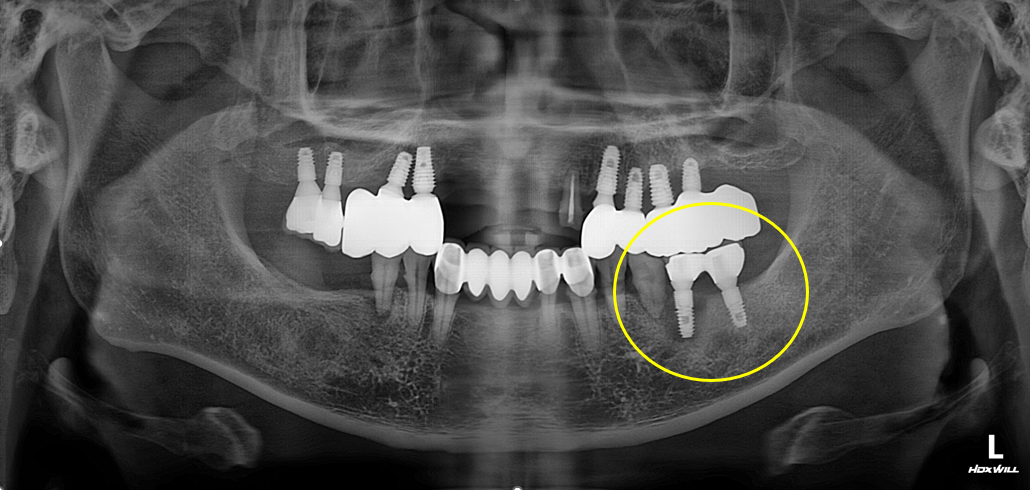

[임플란트] 타치과 임플란트 실패 후 재식립 사례

[임플란트] 전악 임플란트 식립사례

최소식립 전악임플란트는 육안이나 감에 의존하는 것이 아니라 디지털 기술을 통한 모의 수술로 안정성과 정확도를 높인 치료 방법입니다.

특히 네비게이션 임플란트는 잇몸을 절개하지 않거나 최소한으로 절개를 할 수 있기 때문에 출혈과 통증이 적고, 비교적 빠른 시간 안에 회복할 수 있다는 큰 장점을 가지고 있어 만성질환자 혹은 고령자에게도 적합한 치료방법입니다.

최소식립 전악임플란트는 칼로 잇몸을 절개하는 방법이 아닌 임플란트 식립 부분만 작은 홈으로 구멍을 뚫어 시술하는 방법입니다. 이 치료 방법은 수술 후 통증이나 붓기, 출혈이 거의 없어 부담이 없는 수술입니다.

기존의 절개 수술에 비해 수술 시간이 짧고 병원 내원 횟수가 적어 연세가 많으신 고령의 환자 또는 당뇨와 고혈압 같은 전신 질환이 있으신 분들도 안전하게 시술하실 수 있어 최고의 정확성과 안정성을 보장하며 부작용을 최소화합니다.